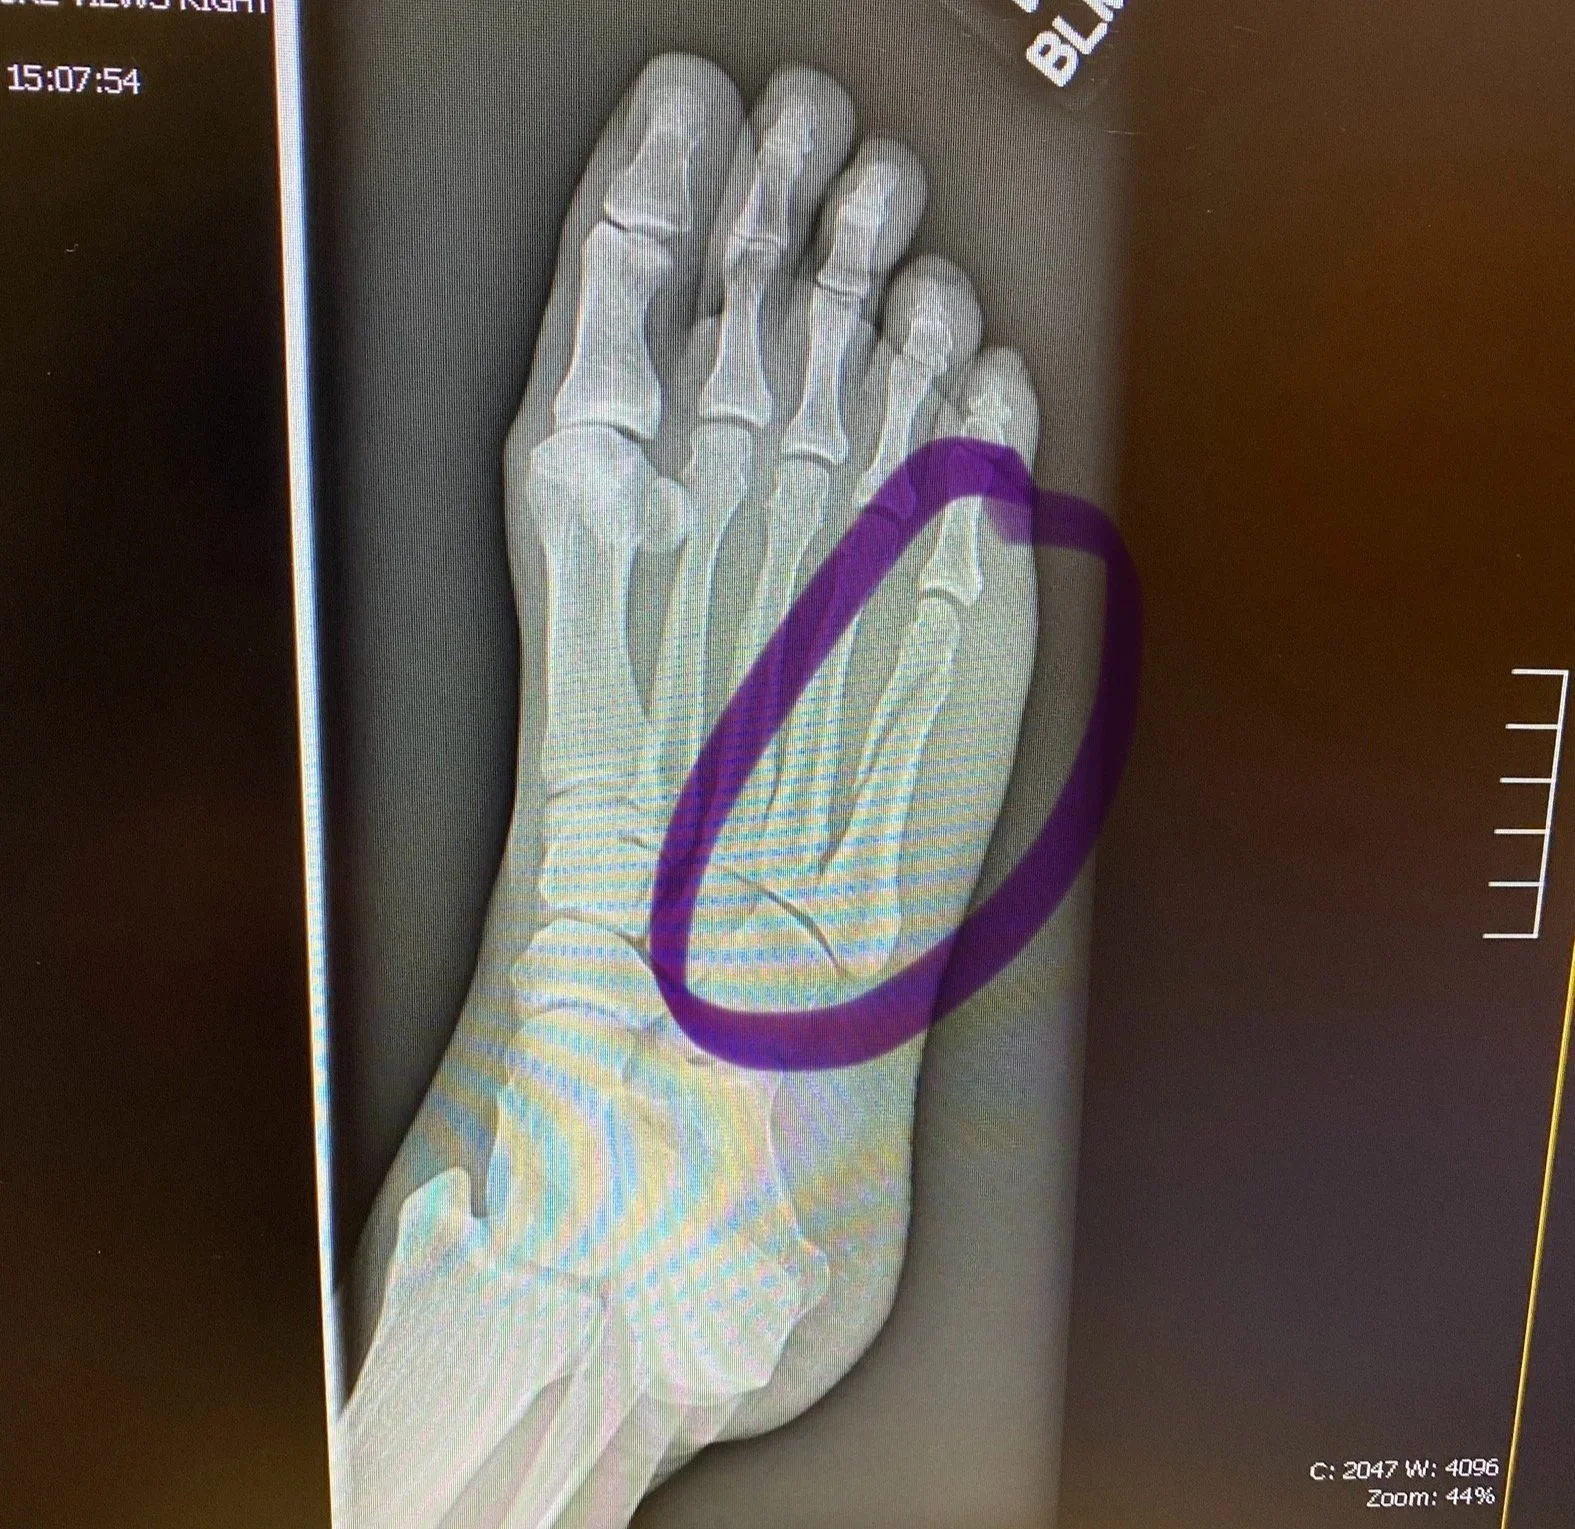

After another day of elevation and suffering, I realized things with the foot weren't trending hopefully, and spent most of a day at a pleasant and understaffed urgent care center. X-rays confirmed a spiral fracture of a metatarsal. I was grateful that my insurance would cover the visit.